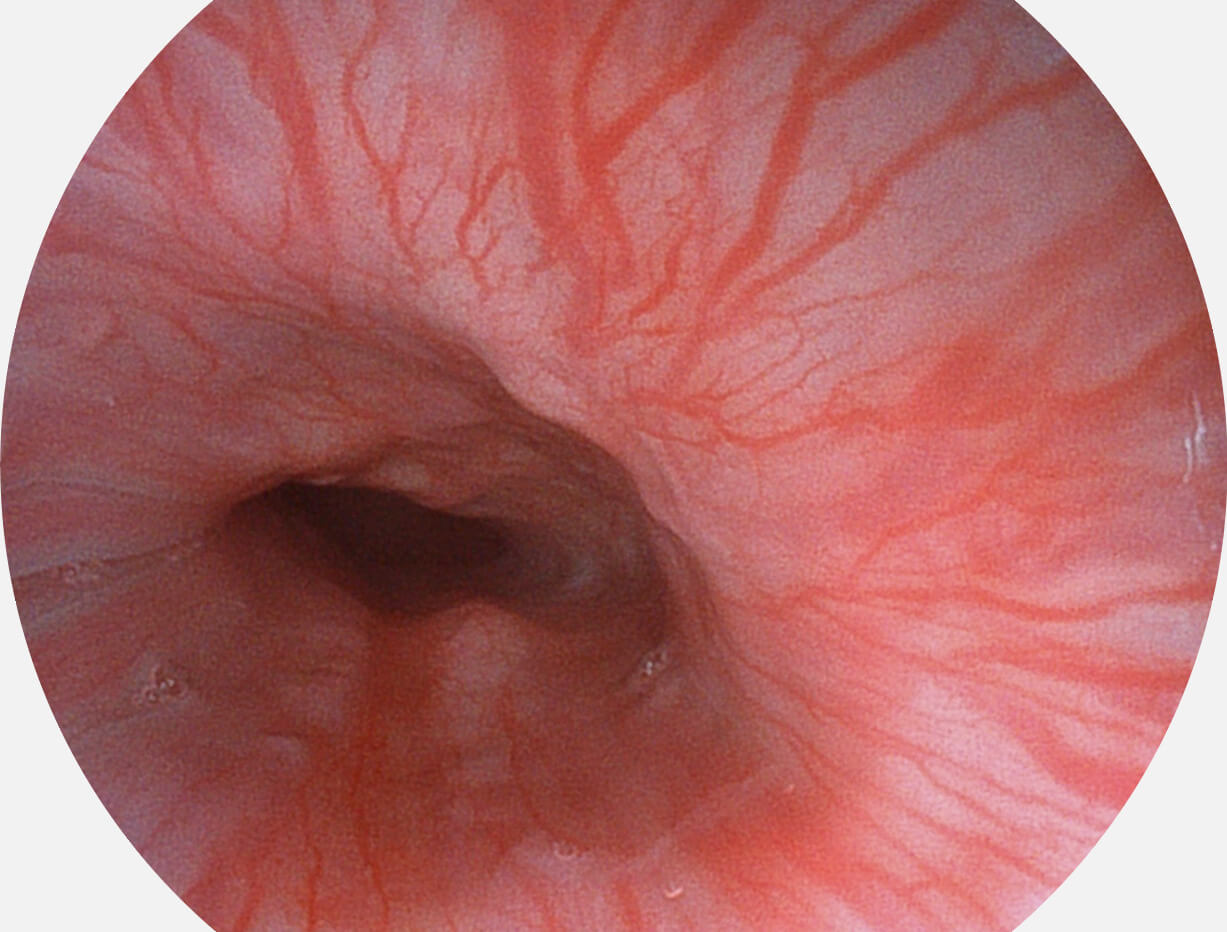

白光图像

SFI图像

图像具有高亮度、高黏膜血管颜色对比度的特点,且不改变粘液、食物残渣、粪便的基本颜色,可在中远景下进行观察,助力消化道早期疾病的诊断。

采用光路合束技术,光谱自由度高,实现了更丰富的照明模式,染色模式SFI及VIST,从远景到近景,助力消化道早期疾病诊断。